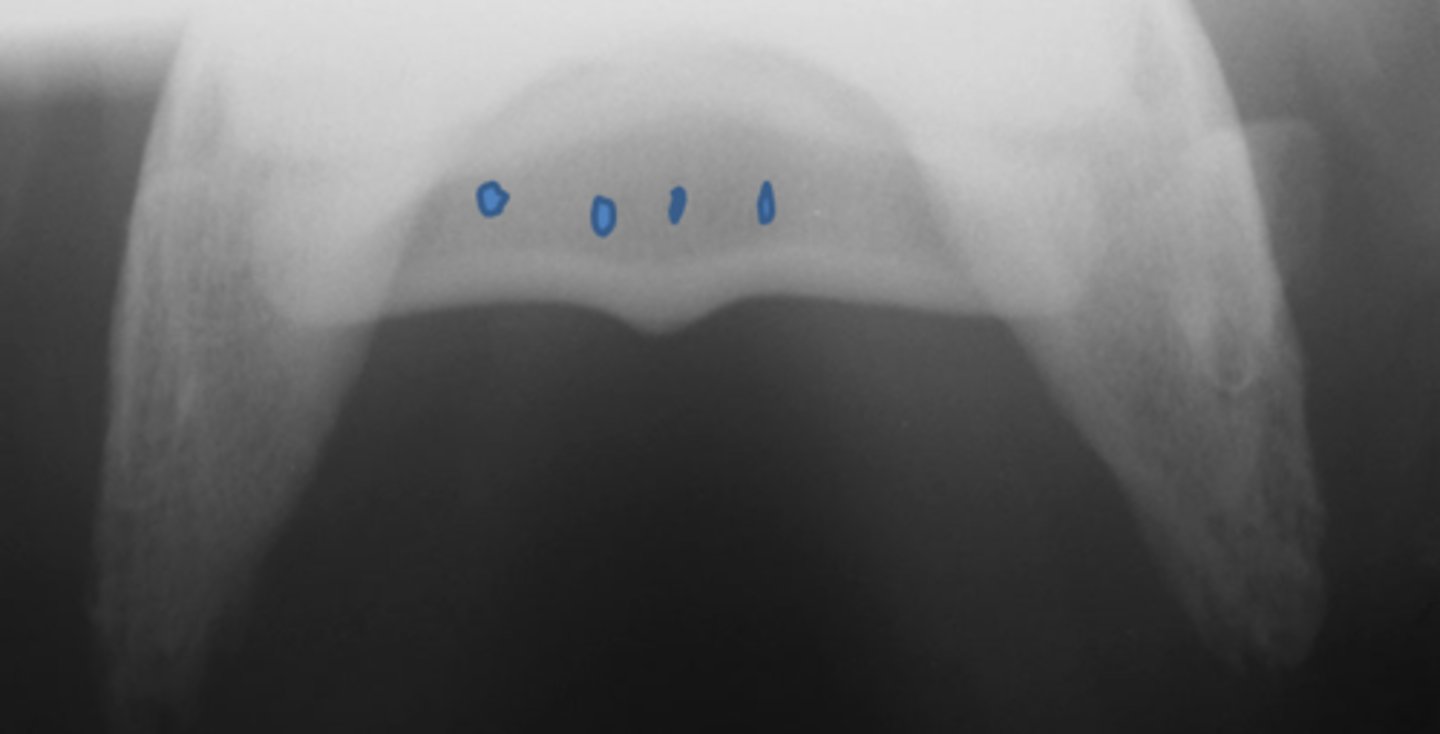

Synovial invaginations

Flexor skyline

What view is this?

1. Flexor surface

2. Corticomedullary distinction

3. Number of synovial invaginations

What is the flexor skyline used to evaluate?

Synovial invaginations